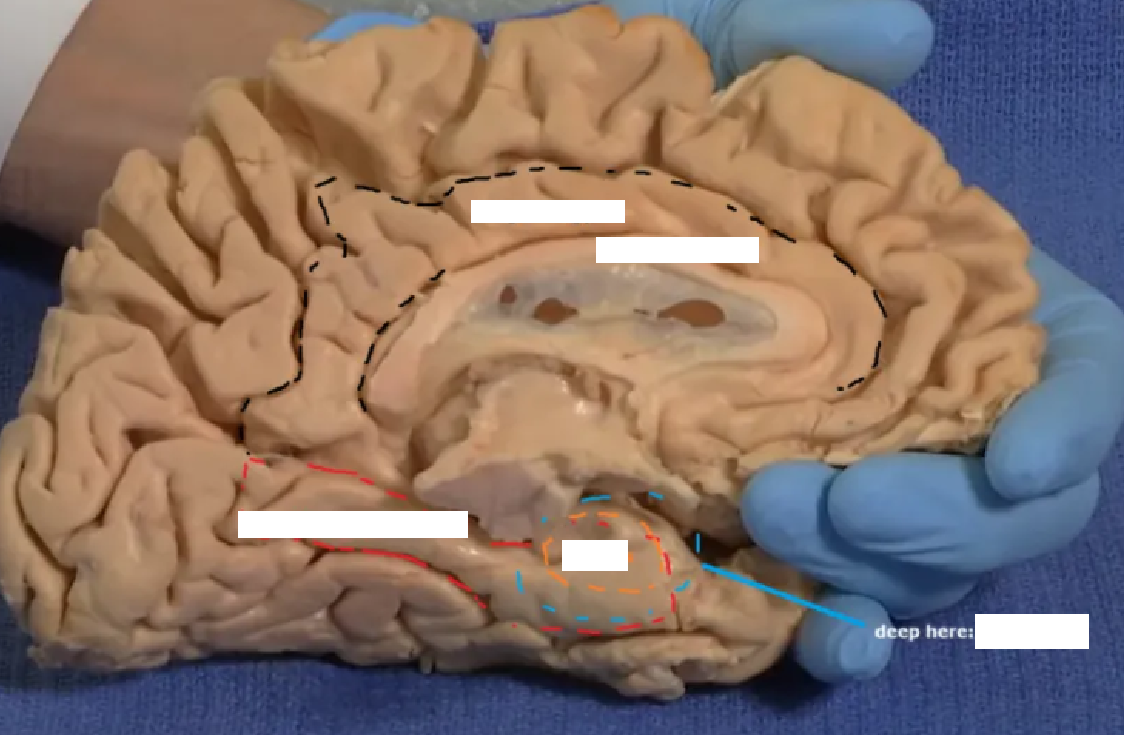

Overlaying the green cingulate and parahippocampal gyri with the purple hippocampus highlights the limbic lobe. Yellow = fornix. Brownish pink = hypothalamus